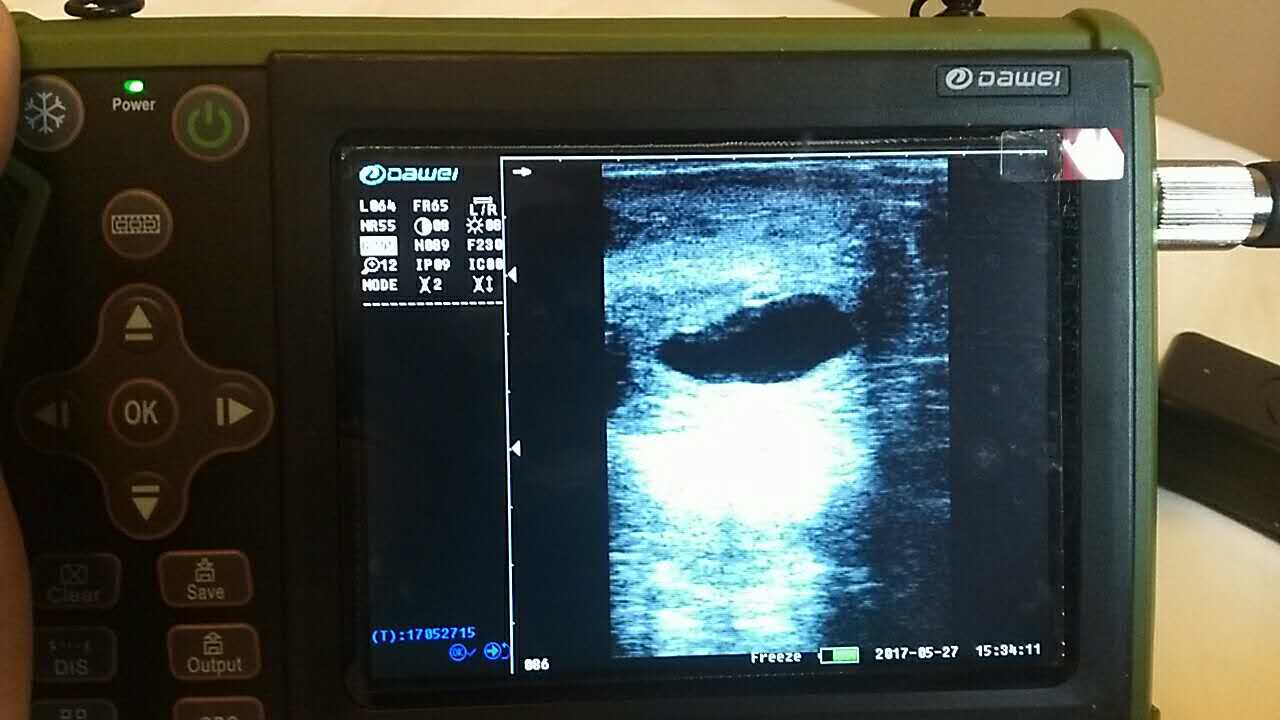

養(yǎng)殖基地140只生產(chǎn)母羊集體接受了B超檢查,利用現(xiàn)代化技術(shù)方法,解決生產(chǎn)母羊繁育難題促進畜牧業(yè)生產(chǎn)結(jié)構(gòu)的調(diào)整。 在檢查中,技術(shù)人員拿著B超儀器,給生產(chǎn)母羊做免費受孕普查。用B超檢測母羊受孕情況,用這種方法給母羊做檢測可以準確掌握母羊是否受孕、母羊生產(chǎn)周期。通過B超早期孕檢和生殖系統(tǒng)疾病診斷,可以清晰的觀測到生產(chǎn)的宮腔和胎兒的生產(chǎn)發(fā)育情況。除了幫助基地對問題羊做出正確診斷,提出合理的治療方案,淘汰無治療價值的長期空懷羊,還能提高受孕率,降低飼養(yǎng)成本,有效規(guī)避了假妊娠造成的經(jīng)濟損失。

檢測懷孕 估測胎仔數(shù) 疾病診斷 胎兒活力鑒定 胎心搏動 適用對象:適用于羊、豬、狗等動物受孕診斷(集成6種常見動物孕周測量數(shù)據(jù)包) 適用范圍:規(guī)模化豬場,人工授精站,飼料/獸藥經(jīng)銷商及企業(yè),科研教學單位 |